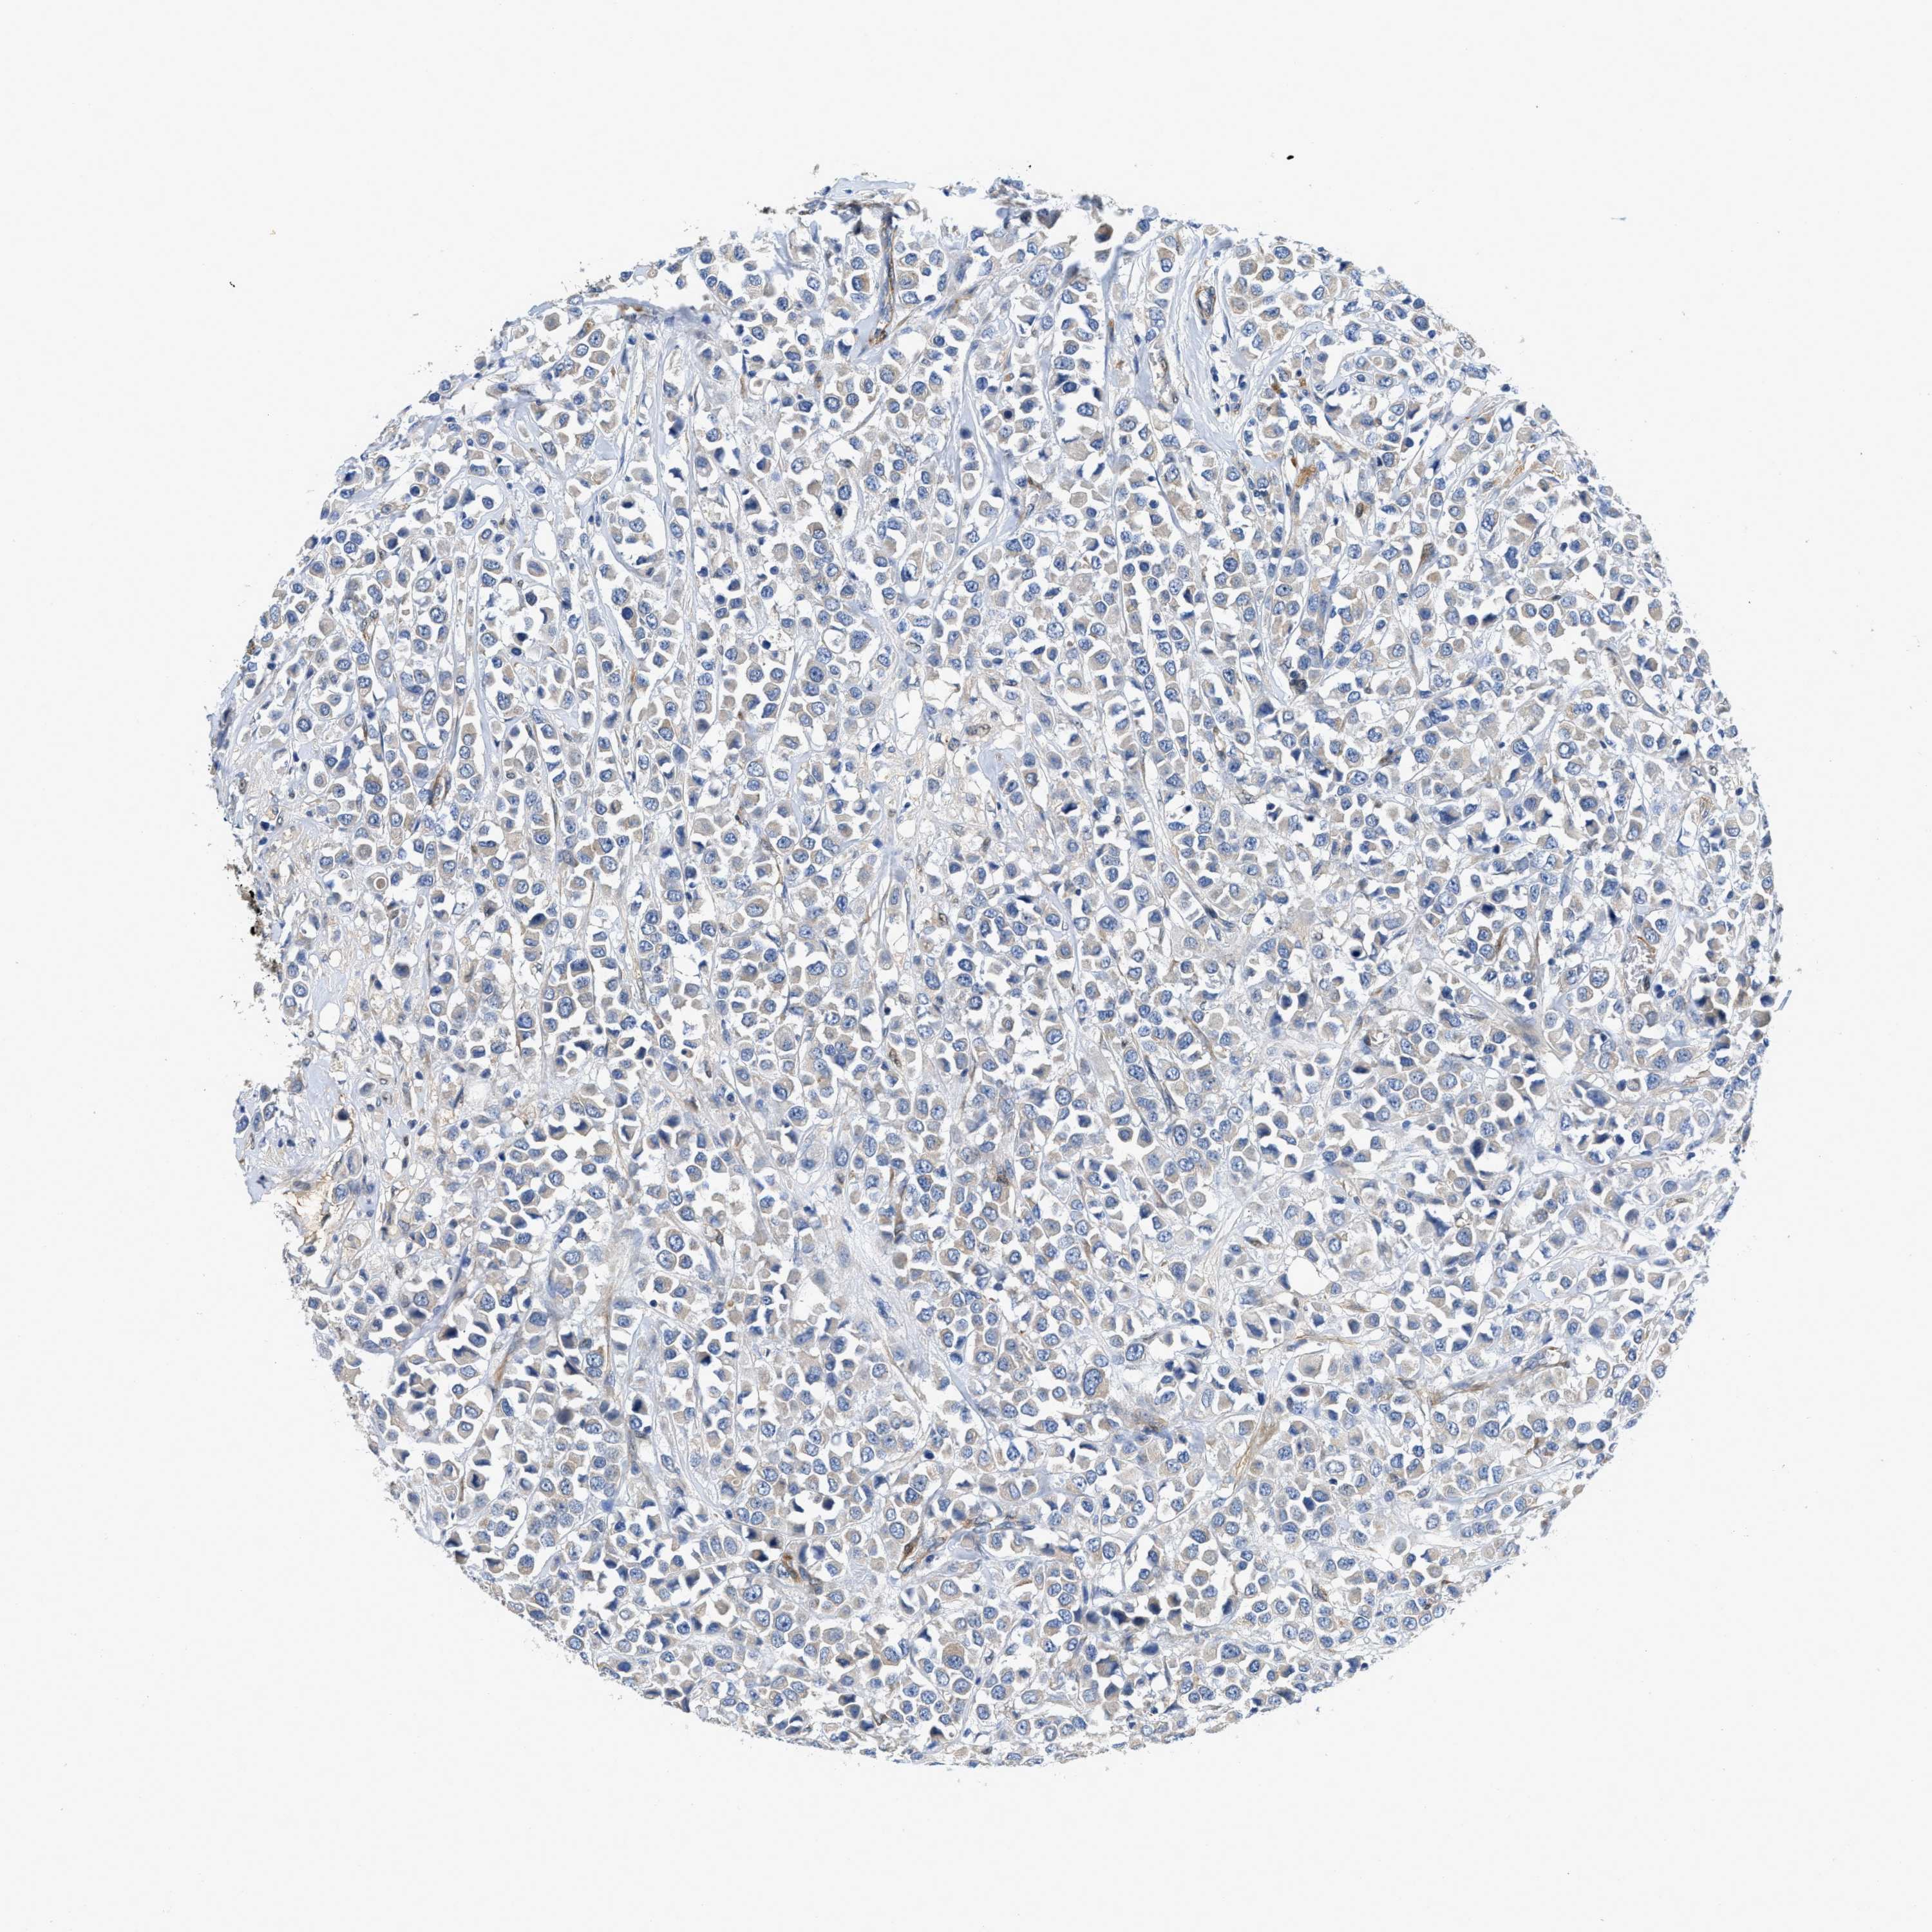

CANCER BREAST CANCER Show tissue menu

BRCA TCGA BRCA VALIDATION PROTEIN EXPRESSION

RAPH1 is not prognostic in Breast Invasive Carcinoma (TCGA)